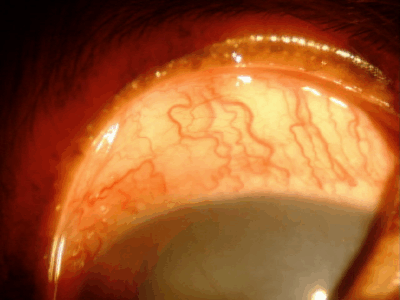

血管新生

角膜には本来血管がなく透明ですが、炎症、傷、刺激などが慢性化すると角膜周囲から血管が伸びてきます。だいたい1日あたり1mm伸びるといわれています。原因としては角膜炎、角膜潰瘍、乾性角結膜炎(ドライアイ)、パンヌスなどがあります。